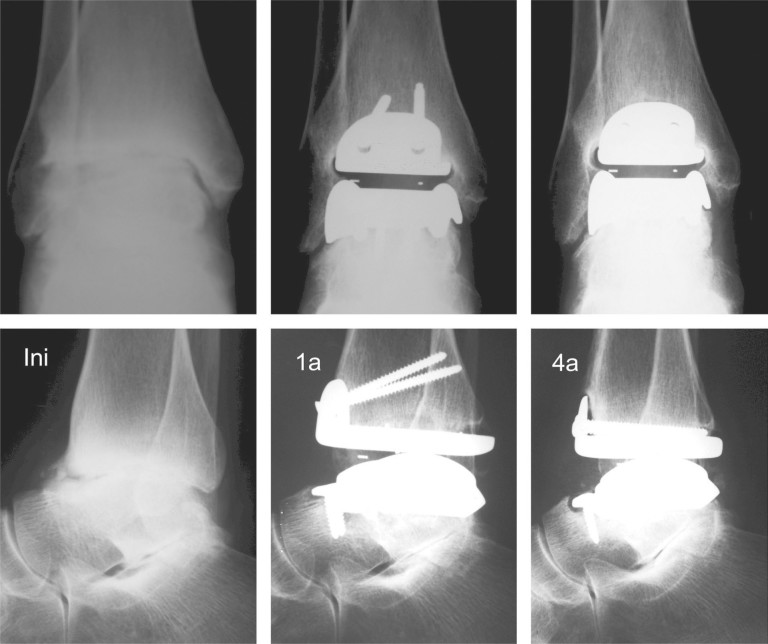

Figure 2.

Patient #4: Radiographs in anteroposterior and lateral views of the right ankle at four different times: initial, three months after the operation, one year after the operation and four years after the operation. Despite good positioning of the prosthetic components, a radiolucent line appeared three months after the operation, in the contact area between the tibial component and the medial edge of the fibula. This line continued to be present one year after the operation and had regressed by the time of the fourth-year assessment, while the patient presented a clinical result that was considered good. See also the joint mobility of this patient demonstrated in Figure 6